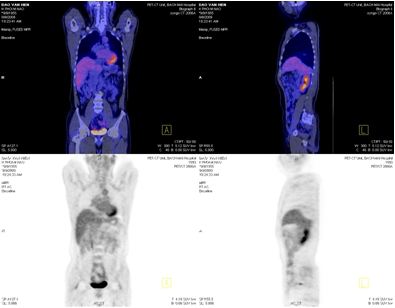

PET/CT

Kết quả: Thành ngực, trung thất và nhu mô phổi 2 bên và các tổ chức ngoài não khác không thấy có hấp thu F-18 FDG bất thường.

· Khối u đã thu nhỏ kích thước (từ 33mm xuống còn 14mm), tổ chức khối u thoái hoá dạng nang (trên PET/CT, max SUV=3,54)

· Không có tổn thương mới

2. Tại phổi

· Khối u tan hoàn toàn

· Không xuất hiện tổn khác tại phổi và ngoài phổi